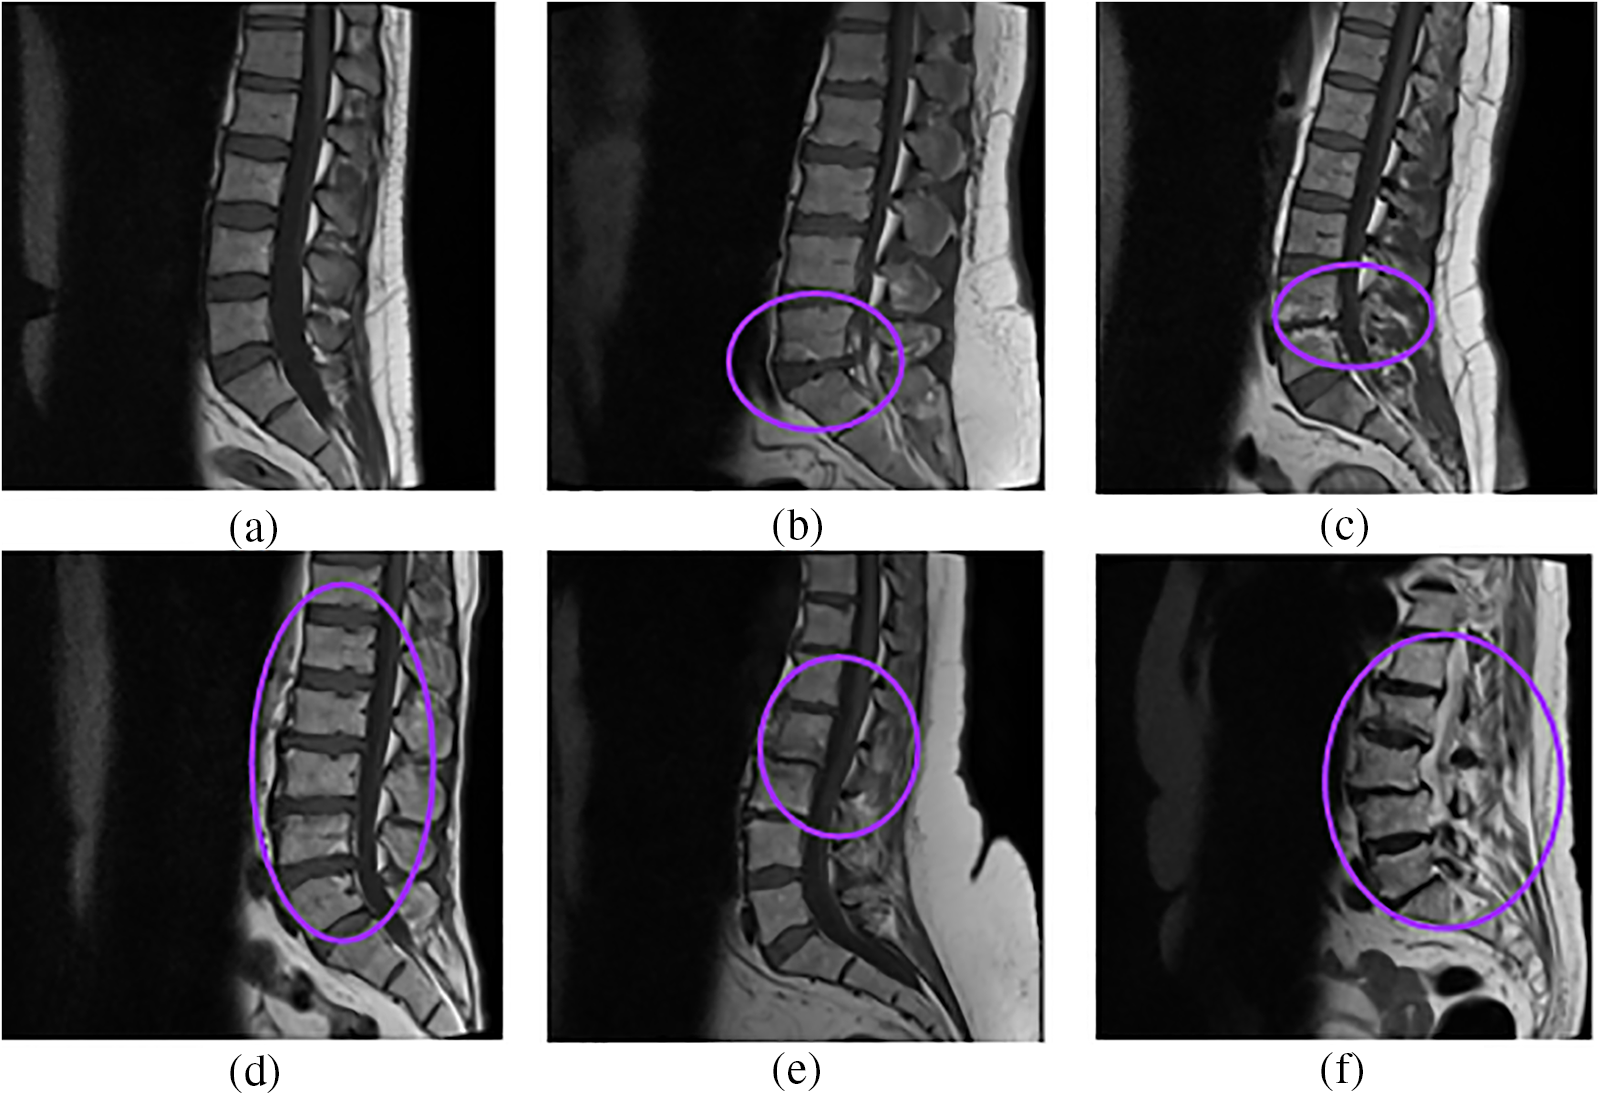

The Lumbar Spine MRI Dataset from the Mendeley Data website in [42] is a publicly available standard dataset containing T1-weighted and T2-weighted mid-sagittal view images of 515 patients. T1-weighted mid-sagittal view comprises either 15 or 30 slices of size

Figure 4: Sample images from the dataset (a) Normal, (b) Disc Herniation, (c) Degenerative disc disease, (d) Disc Bulging, (e) Spondylolisthesis, (f) Fractured